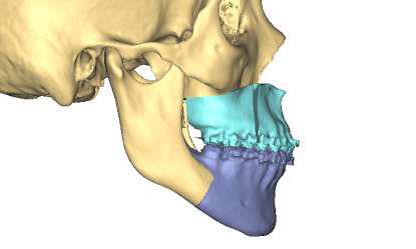

Virtual Treatment Planning

Prediction and Preoperative Workup with Model Surgery

The surgical team spends much time and energy in collaboration with the orthodontist to plan the surgery.  A joint treatment plan is devised.  The orthodontist sets up for the surgery with braces.  The surgical team then plans the surgery using xrays to predict the movements, performs the surgery on models, then fabricates acrylic splints to guide the surgical team in the operating room.